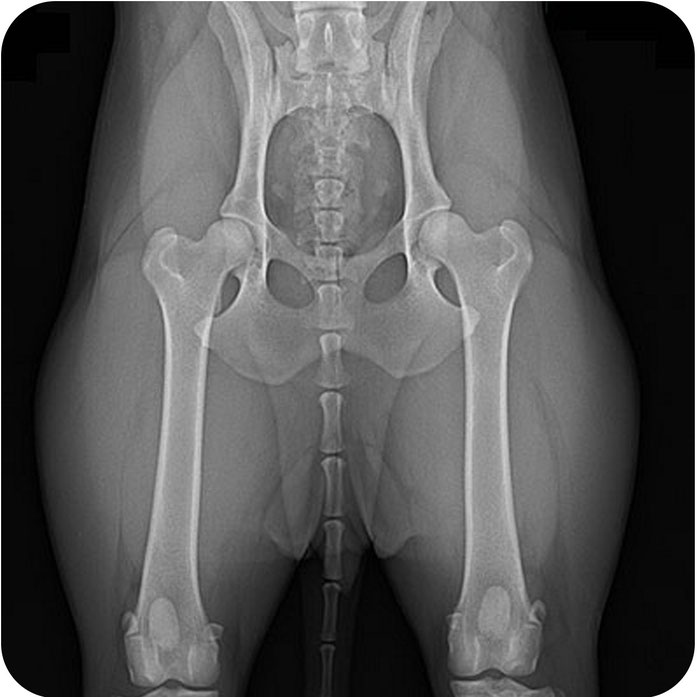

Röntgen - High Definition

Schnelle Basisdiagnostik für Knochen, Lunge und Bauchraum

Typische Einsatzbereiche

• Knochenbrüche, Arthrosen oder Gelenkveränderungen

• Untersuchung von Herz, Lunge und Brustkorb

• Kontrolle bei Atemnot, Husten oder Flüssigkeit im Thorax

• Darstellung von Fremdkörpern oder Magen-Darm-Problemen

• Orthopädische Voruntersuchungen (z. B. HD-/ED-Röntgen)